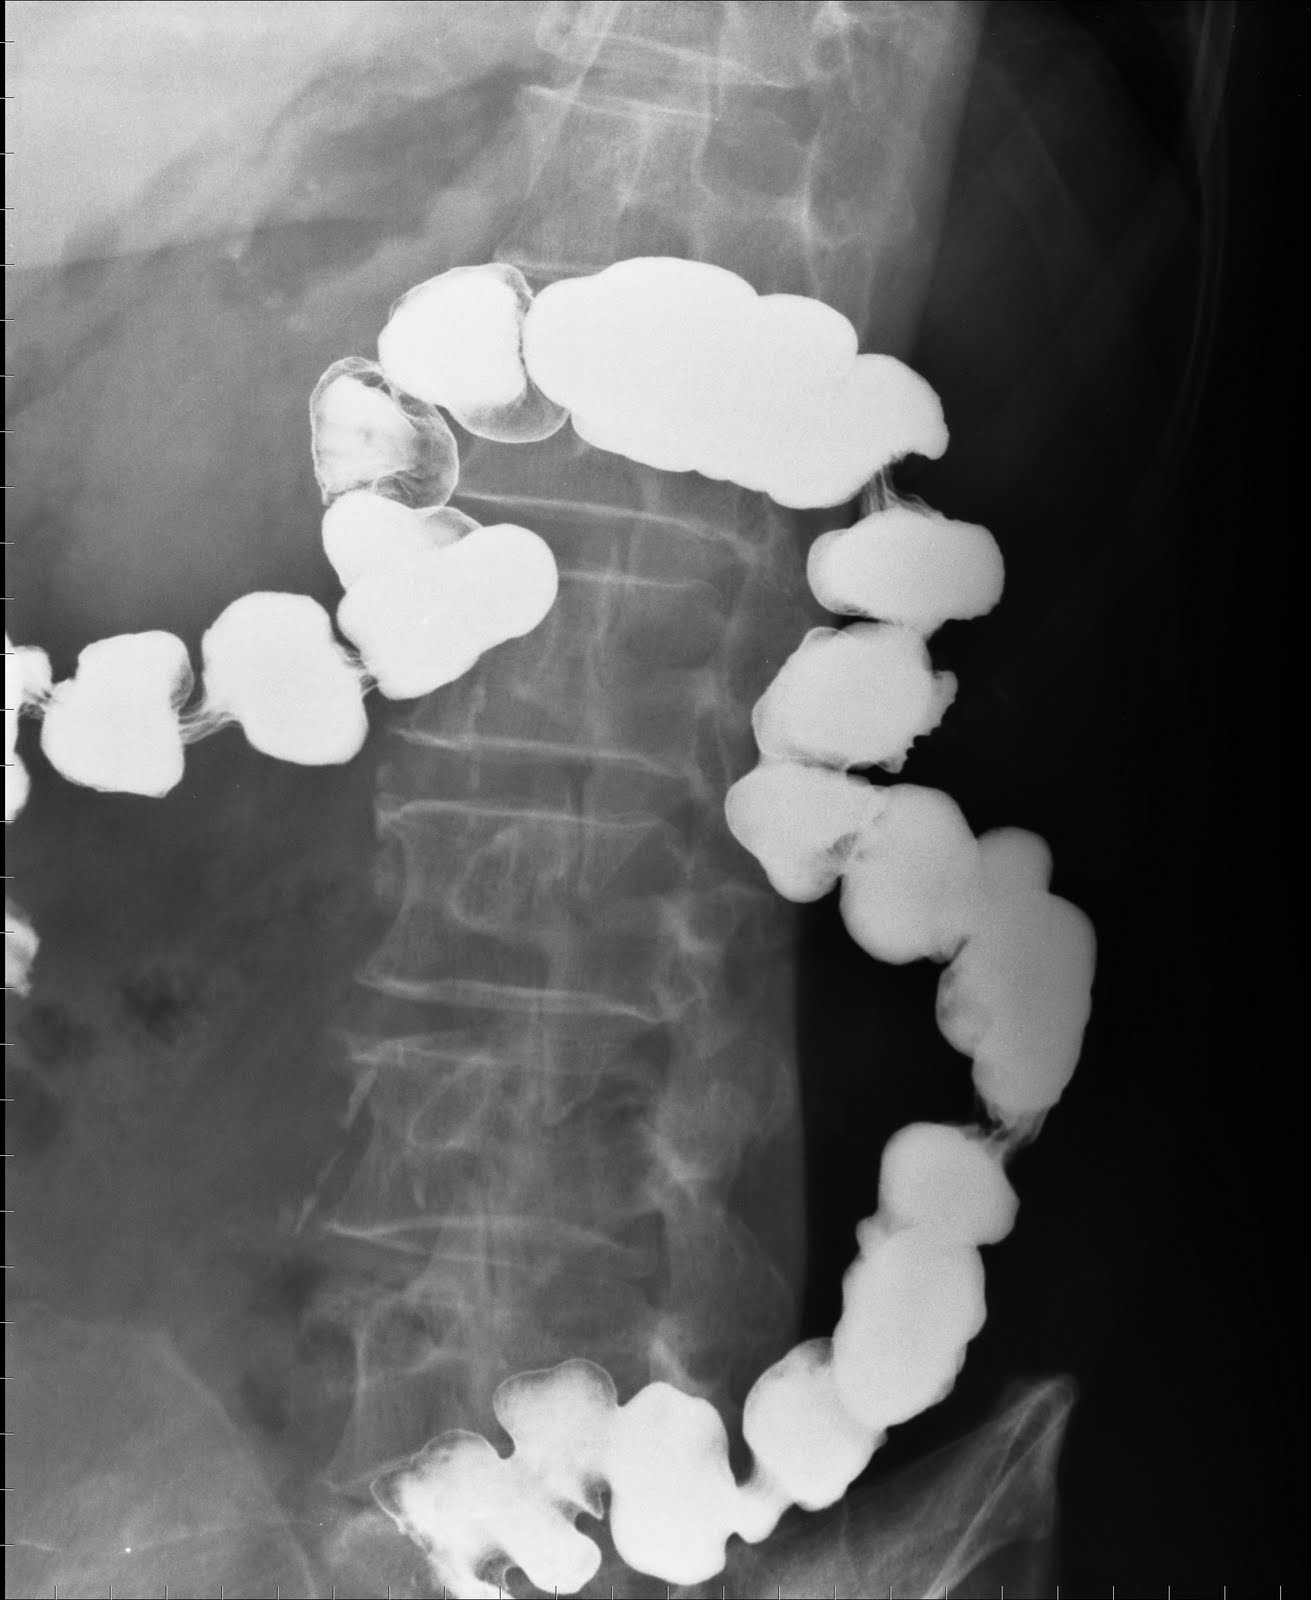

Barium enema. The cecum, ascending colon, transverse colon, and... Download Scientific Diagram Colon In Loop Vs Barium Enema barium enema (be) is widely available for diagnosis of colorectal cancer despite concerns about its accuracy and. the findings on barium enema were positive in 222 (26 percent) of the paired examinations, including 94 of the 242 colonoscopic. Colon In Loop Vs Barium Enema.

Normal Double Contrast Barium Enema Stock Image F031/9962 Science Photo Library Colon In Loop Vs Barium Enema the findings on barium enema were positive in 222 (26 percent) of the paired examinations, including 94 of the 242 colonoscopic. barium enema (be) is widely available for diagnosis of colorectal cancer despite concerns about its accuracy and. Colon In Loop Vs Barium Enema.

Healthy colon, barium enema Stock Image C001/1835 Science Photo Library Colon In Loop Vs Barium Enema barium enema (be) is widely available for diagnosis of colorectal cancer despite concerns about its accuracy and. the findings on barium enema were positive in 222 (26 percent) of the paired examinations, including 94 of the 242 colonoscopic. Colon In Loop Vs Barium Enema.

Redundant colon on double contrast barium enema Image Colon In Loop Vs Barium Enema barium enema (be) is widely available for diagnosis of colorectal cancer despite concerns about its accuracy and. the findings on barium enema were positive in 222 (26 percent) of the paired examinations, including 94 of the 242 colonoscopic. Colon In Loop Vs Barium Enema.